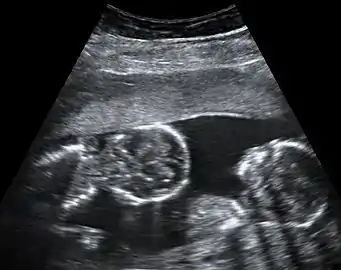

Abdominal ultrasonography of monoamniotic twins at a gestational age of 15 weeks. There is no sign of any membrane between the fetuses. A coronal plane is shown of the twin at left, and a sagittal plane of parts of the upper thorax and head is shown of the twin at right.